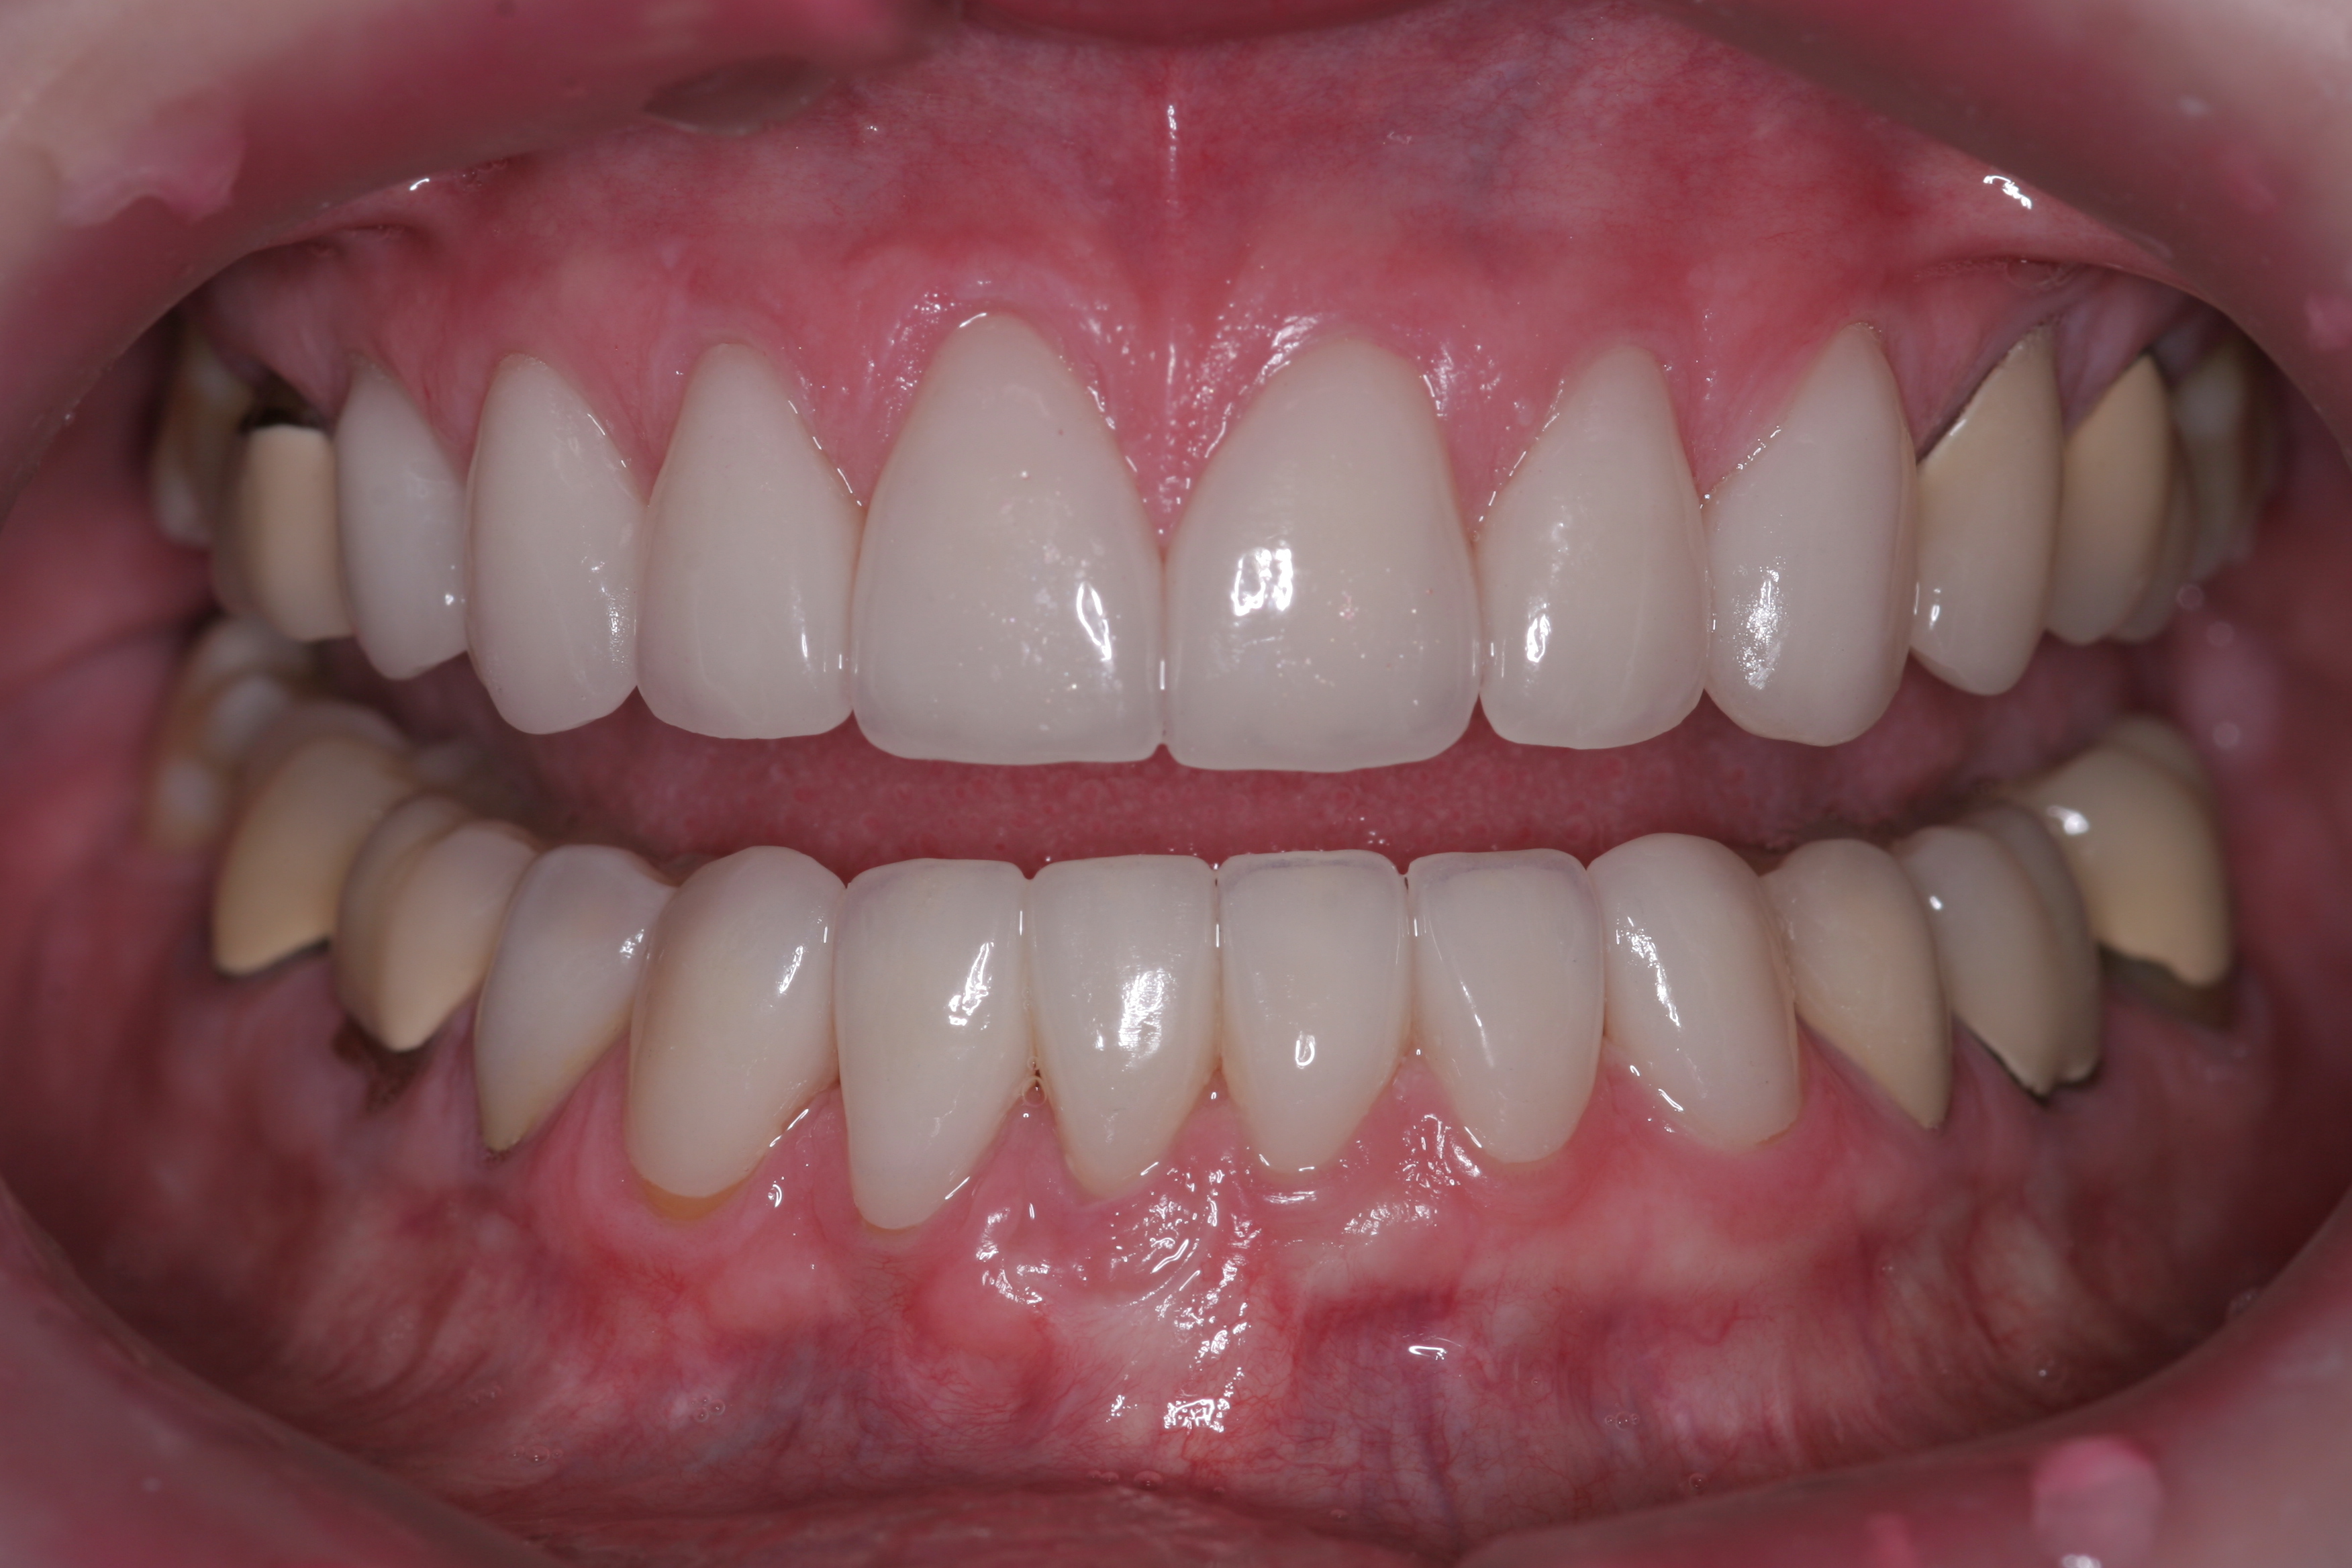

(22.) The final restorations, which reflect the changes modeled through the provisional phase.

Figure 22

(23.) The final restorations, which reflect the changes modeled through the provisional phase.

Figure 23

(24.) The final restorations, which reflect the changes modeled through the provisional phase.

Figure 24

(25.) The final restorations, which reflect the changes modeled through the provisional phase.

Figure 25

(26.) The final restorations, which reflect the changes modeled through the provisional phase.

Figure 26

(27.) The final restorations, which reflect the changes modeled through the provisional phase.

Figure 27

(28.) The final restorations, which reflect the changes modeled through the provisional phase.

Figure 28

(29.) The final restorations, which reflect the changes modeled through the provisional phase.

Figure 29